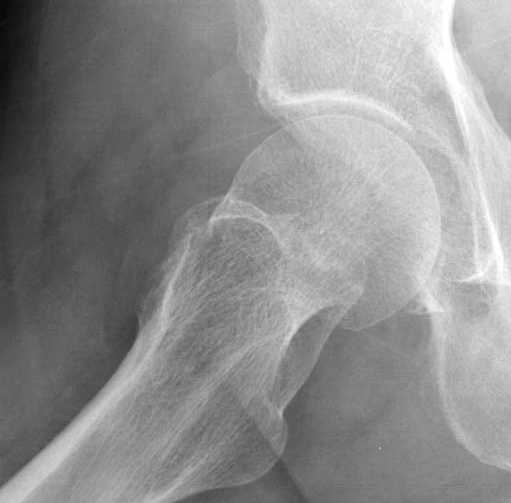

Уважаемые коллеги,

Хотели бы знать тактику лечения 62 летнего больного, отягощенного

алкоголизмом, с жалобами на боли в правом тазобедренном суставе.

Не смогли добиться вразумительного ответа по поводу анамнеза травмы,

клинически движения ограничены из-за боли, сделанные снимки сустава

представлены. На КТ неполный перелом шейки. Начали профилактику

возможного Алкогольного Делирия.

Дальнейшее рекомендации, оставить как есть, или профилактическая

перкутанная фиксация?